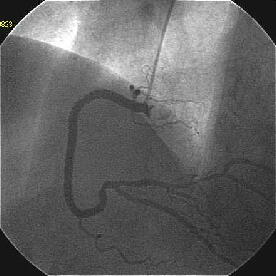

�ŏI�o���オ���IVUS�BIVUS��170507��septal���}����170509������2mm��O��

���̕����B

|

|

|

|